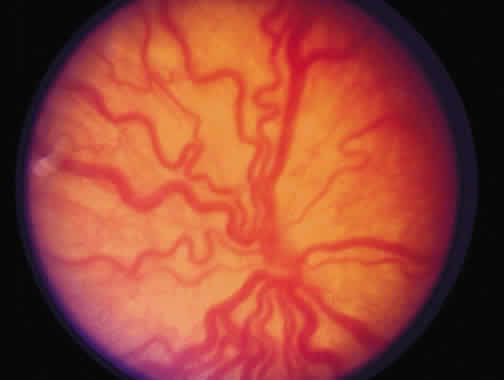

The most common form of regression of ROP is continued growth of the retinal vasculature anteriorly with gradual fading of the disease at the border of posterior vascularized and anterior avascular retina. Another more dramatic sign of regression is the growth of vessels beyond the ridge (Fig. 1). The vessels penetrate into the avascular retina as an arteriole with an accompanying venule. As the vessels grow beyond the ridge, the dilation and tortuosity of vessels just posterior to the shunt and in the posterior pole diminish.

Fig. 1. Regressing retinopathy of prematurity. The vessels have crossed the ridge and are growing into the avascular zone.